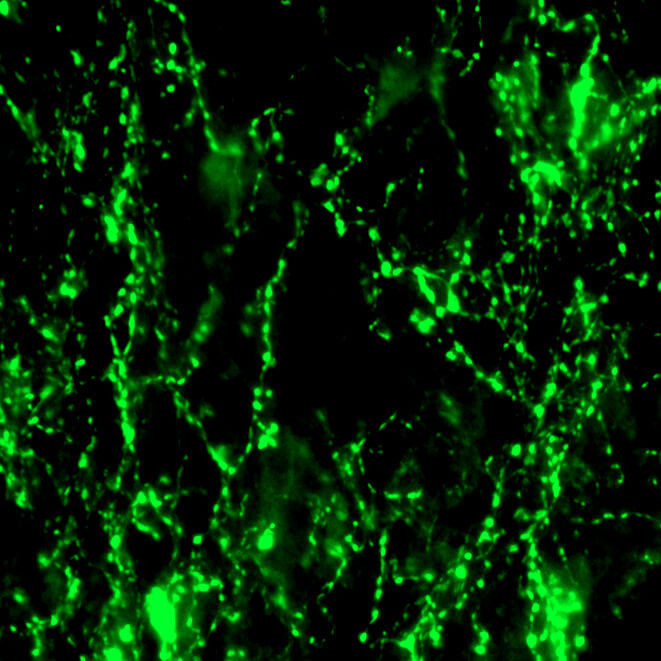

Physical therapy can improve both motor and sensory function after spinal cord injury, even at the chronic stage. Our group is studying optimal combination that can improve forelimb function after cervical spinal cord injury in a rat model. We are also interested in uncovering neural substrates that can mediate functional recovery in the chronically injured spinal cord.